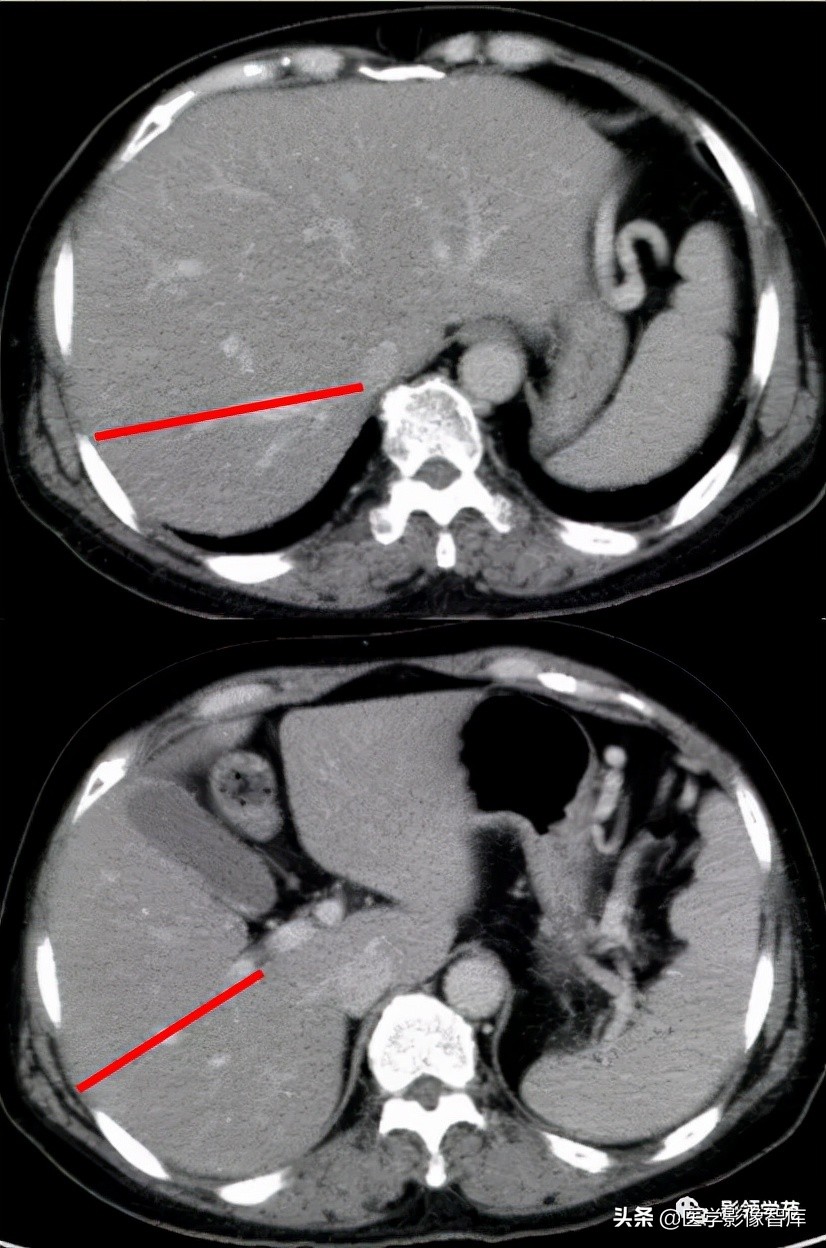

5、右段间裂:又称横裂,肝门静脉右支或肝门右切迹作为右段间裂的标志,即平面以上为右半肝的后上段和前上段;以下为后下段和前下段。

CT:首先找出肝脏的三大静脉:肝中静脉,肝左静脉,肝右静脉,找出门静脉及其分叉部位。门静脉分叉部位可以区分上段和下段,即肝S8/S5,S7/S6,门静脉分叉以上为S8、S7;肝右静脉和肝中静脉之间是右前叶,肝右静脉以后是右后叶

一般规律,从CT上看,最先看到的是S8然后是S2、3,肝左外叶以肝裂为界,左内叶为肝裂和肝中静脉之间的区域,胆囊往下的层次是S5,最后的层面一般是S6,下腔静脉和门静脉夹着的是尾状叶,即S1。